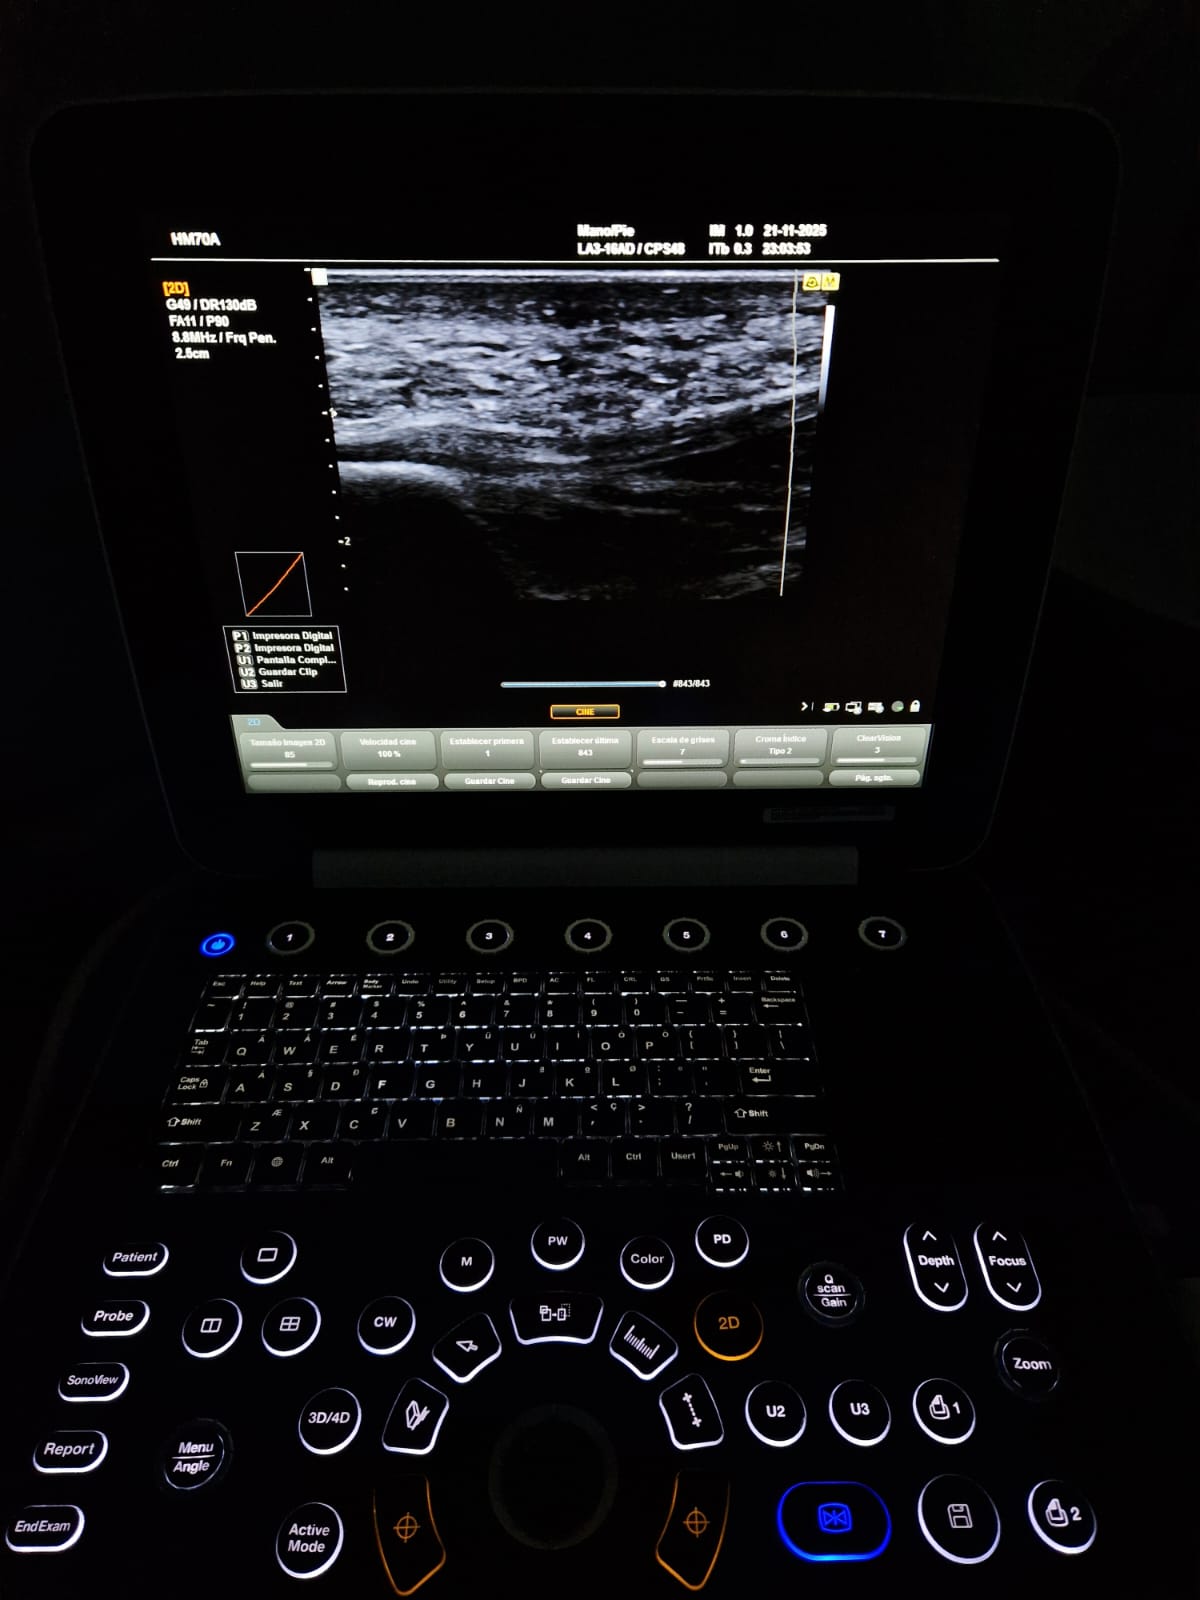

HQ-Vision ™

HQ-Vision ™ proporciona imágenes claras al mitigar las características de las imágenes de ultrasonido que están ligeramente borrosas que la visión real.

Visión de aguja

- El ecógrafo Samsung HM70 EVO es un dispositivo portátil de alto desempeño, diseñado para cubrir una amplia variedad de aplicaciones clínicas y adaptarse a distintos tipos de pacientes. Cuenta con un flujo de trabajo eficiente, gran resistencia y una calidad de imagen de alta definición, lo que permite su uso en múltiples entornos y escenarios clínicos.

- Sonda Lineal LA3-16AD y Stick LS6-15.